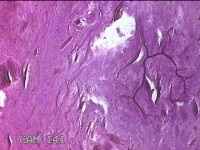

性别

男

年龄

46岁

临床诊断

皮下结节

一般病史

发现右侧中指指间关节背侧一包块,伴间断性疼痛不适,考虑痛风结节。

标本名称

右侧中指指间关节背侧包块

大体所见

灰白粉红色包块0.8x0.7x0.3cm一堆。